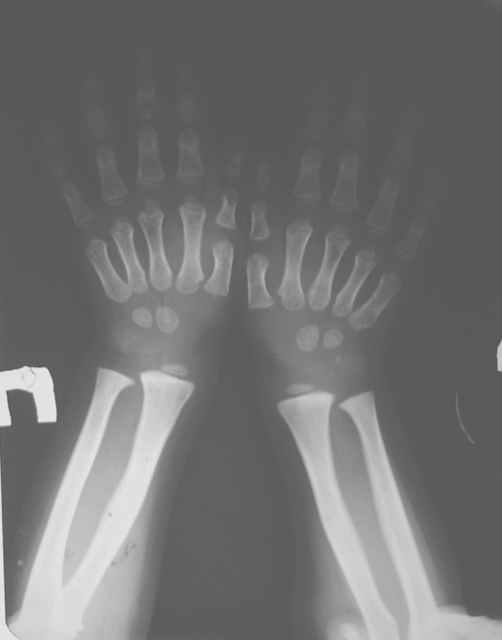

Мальчик, 5 лет. Гипохондроплазия. Генетическая предрасположенность к нарушению физического развития. Ребенок от I беременности, протекавшей нормально. ТОРЧ-негативный. Неврологических расстройств нет. Семейный анамнез: средний рост мужчин в семье 150 см, антропологические особенности - короткие конечности, длинное туловище, крупный череп. Вес 15 кг, рост 92 см.Тактика лечения? Заранее благодарю! С уважением,А.В.Владзимирский